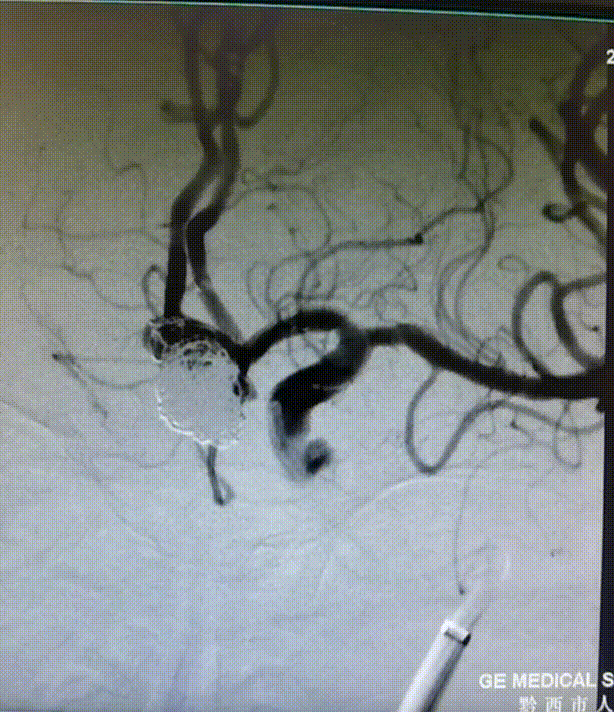

遂小心撤出微导丝,再次复查造影,显影如前。以血管缝合器缝合右股动脉,常规加压包扎。术毕,全麻清醒如术前,安返病房。

复查造影。